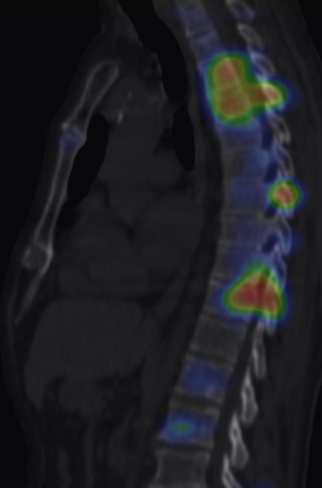

More complex anatomic structures (spine, the base of the skull, facial and hip bones) can be imaged more confidently with SPECT scans. On one hand, they provide a more accurate spatial localization and on the other, with their superior contrast resolution, they are able to differentiate lesions even if planar exams are negative or uncertain. SPECT-CT can characterize the CT morphology of the lesions with pathologic uptake. Thus, it is capable to provide a definitive diagnosis. (Figure 4.)

Image

a

b

c

d

e

4. Bone scintigraphy, prostate cancer. The image set shows the characterization of multiplex increased activity uptake. Posterior whole body scan (a). SPECT-CT coronal fusion images (b,d), CT examination (c,e). Sclerotic lesions in the pelvic bones are suggestive of osteoplastic metastases (b,c), small joint arthrosis at LIII-IV segments, more expressed on the left side (b,c), spondylosis on the right side at LIV-V segments (d,e). (The increased activity spot on the whole body scan, at the left cubital region, is correspondent to the paravasation of the iv. radiopharmaceutical.)